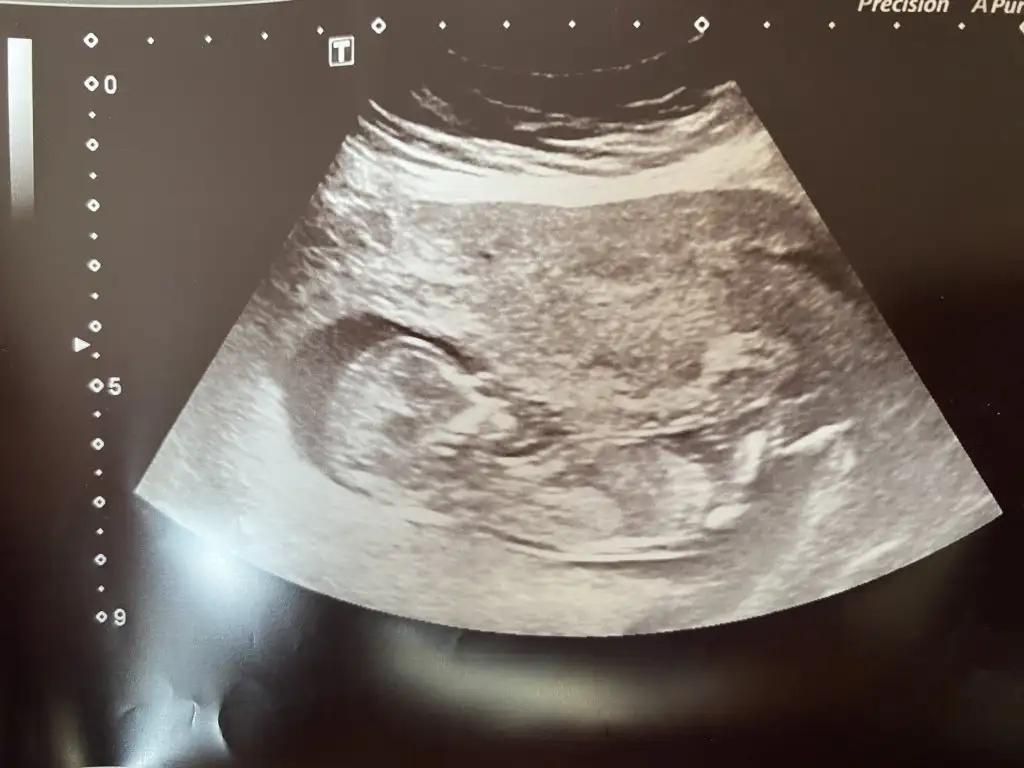

Benimkide 12 haftalık sizce erkekmi kızmı ? ☺️